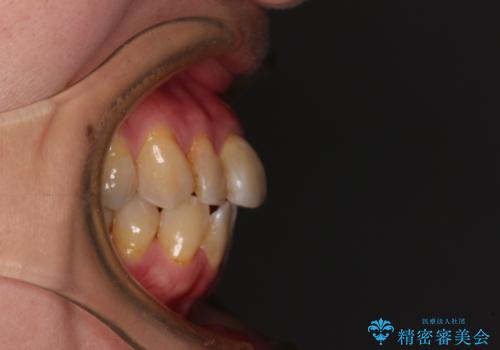

- 口元の突出感を気にして来院された患者様です。

上下前歯が著しく前突している状態であったので、上下左右の小臼歯4本を抜歯し、ワイヤー装置にて矯正治療を行うこととしました。

上顎左側は第二小臼歯に大きなむし歯があったため、通常は第一小臼歯を抜歯するところ、イレギュラーに第二小臼歯を抜歯することとしました。